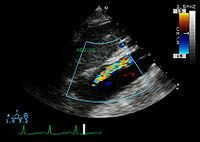

Ultrasound

An echocardiogram displaying the true lumen and false lumen of an aortic dissection: In the image to the left, the intimal flap can be seen separating the two lumens. In the image to the right, color flow during ventricular systole suggests that the upper lumen is the true lumen.

The transesophageal echocardiogram (TEE) is a good test in the diagnosis of aortic dissection, with a sensitivity up to 98% and a specificity up to 97%. It has become the preferred imaging modality for suspected aortic dissection. It is a relatively noninvasive test, requiring the individual to swallow the echocardiography probe. It is especially good in the evaluation of AI in the setting of ascending aortic dissection, and to determine whether the ostia (origins) of the coronary arteries are involved. While many institutions give sedation during transesophageal echocardiography for added patient comfort, it can be performed in cooperative individuals without the use of sedation. Disadvantages of TEE include the inability to visualize the distal ascending aorta (the beginning of the aortic arch), and the descending abdominal aorta that lies below the stomach. A TEE may be technically difficult to perform in individuals with esophageal strictures or varices.